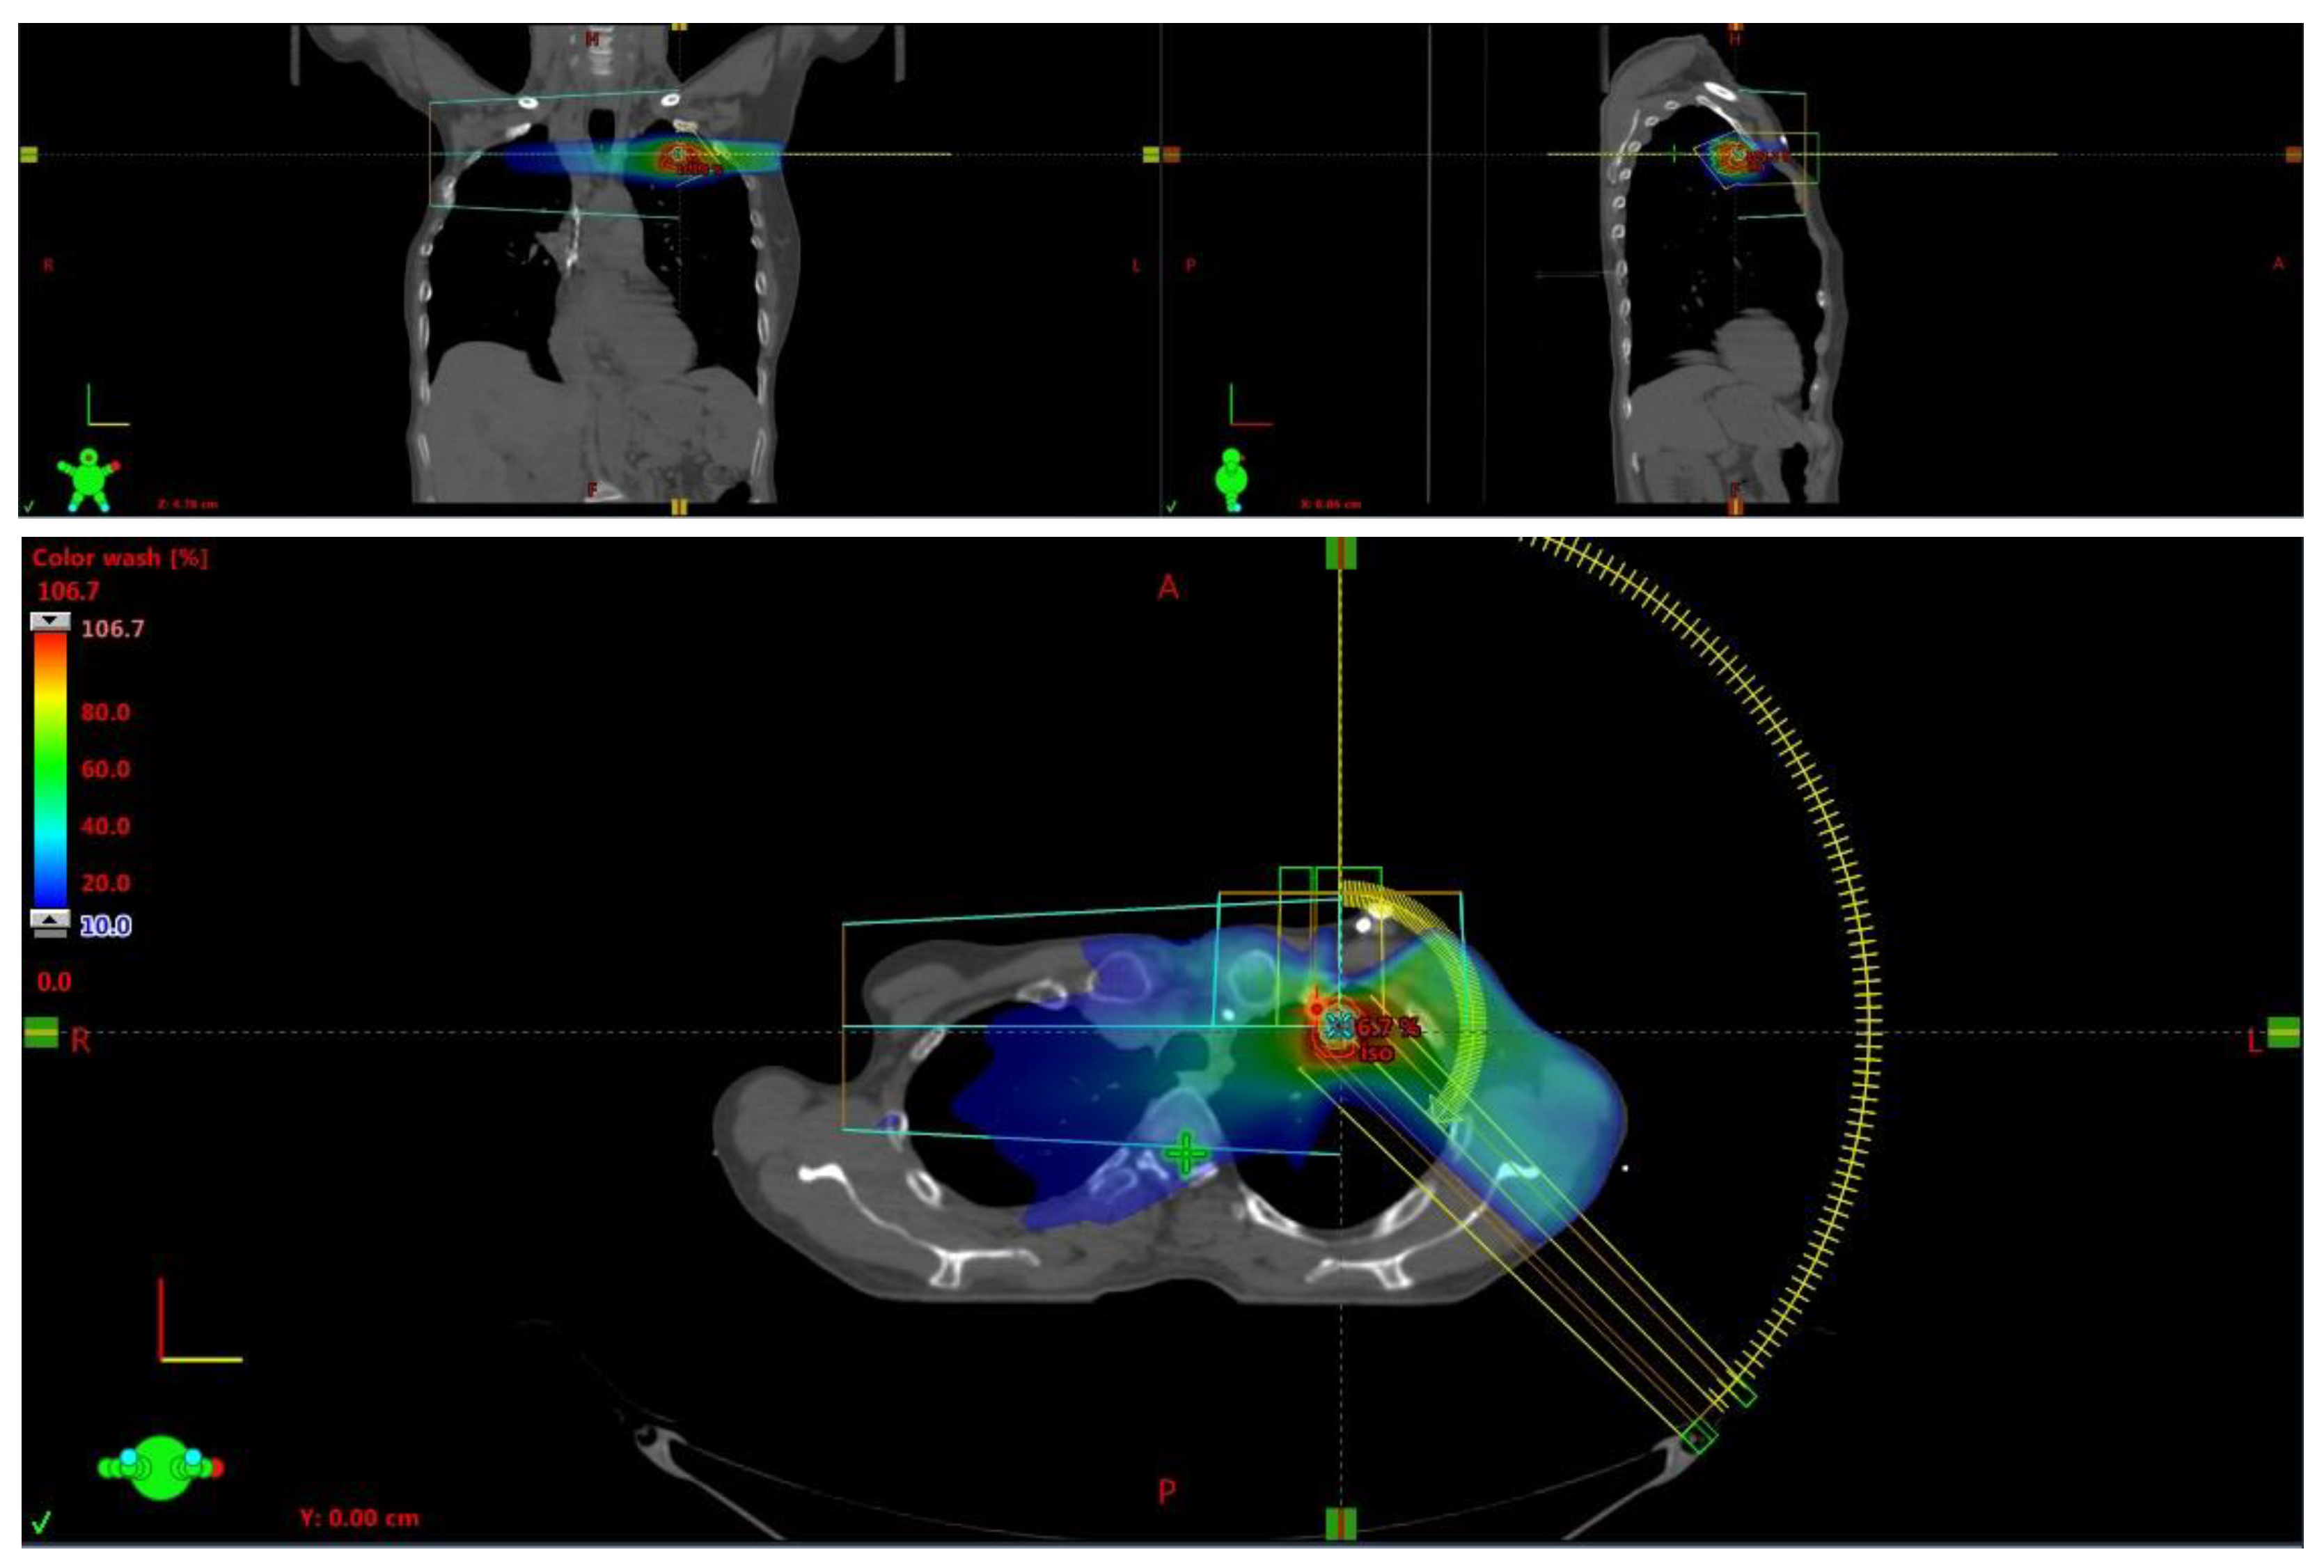

| Radiotherapy Characteristics | ||

| Radiotherapy techniques | 3D-CRT | 9 pts (15.6%) |

| IMRT | 1 pt (1.7%) | |

| VMAT/SBRT | 49 pts (83%) | |

| Lung RT treatments | SBRT 50 Gy in 5 fr | 3 pts (100%) |

| Nodes RT treatments | SBRT 50–35 Gy in 5 fr | 8 pts (72.7%) |